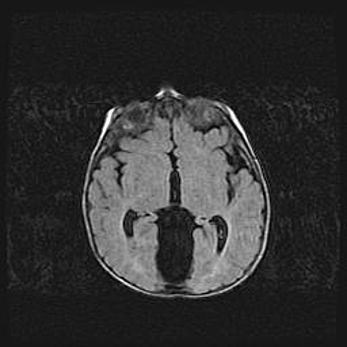

Церебральная ишемия II.

Возраст: 5 дней

Вес: 3400 г

Пол: женский

Окружность головы: 35 см

Срок гестации: 39 недель

Церебральная ишемия – это заболевание, характеризующееся недостаточностью (гипоксией) либо полным прекращением (аноксией) снабжения мозга кислородом по причине закупорки одного или нескольких сосудов. Это приводит к  что метаболическим расстройствам различной степени тяжести в тканях головного мозга, развитию коагуляционных некрозов и гибели нейронов.